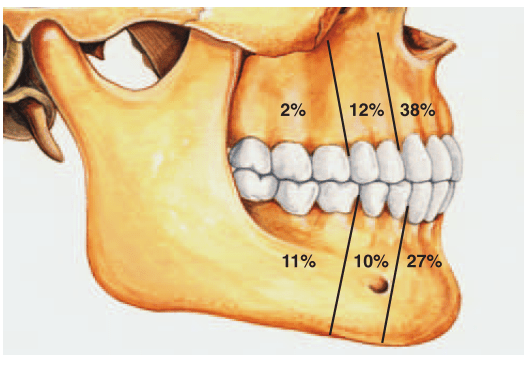

CLINICAL FEATURES:-

Most common tumor.

 Rate of occurance: 60-70%- parotid glands

40-60%- submandibular glands

40-70%- minor salivary glands

seldomly- sublingual glands

 Age: 30-50 years

 Sex: female> male – 3:1 – 4:1

 In parotid- presents in the lower lobe of the superior lobe

as a mass over the angle of the mandible, below and infront

of the ear.

Clinical presentation: painless, slow growing, firm